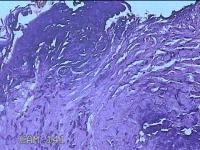

性别

男

年龄

44岁

临床诊断

皮脂腺囊肿

一般病史

右面部起疹12月,不痒。

标本名称

面部肿物

大体所见

灰白粉红色肿物0.5x0.3x0.2cm一个,表面糜烂。